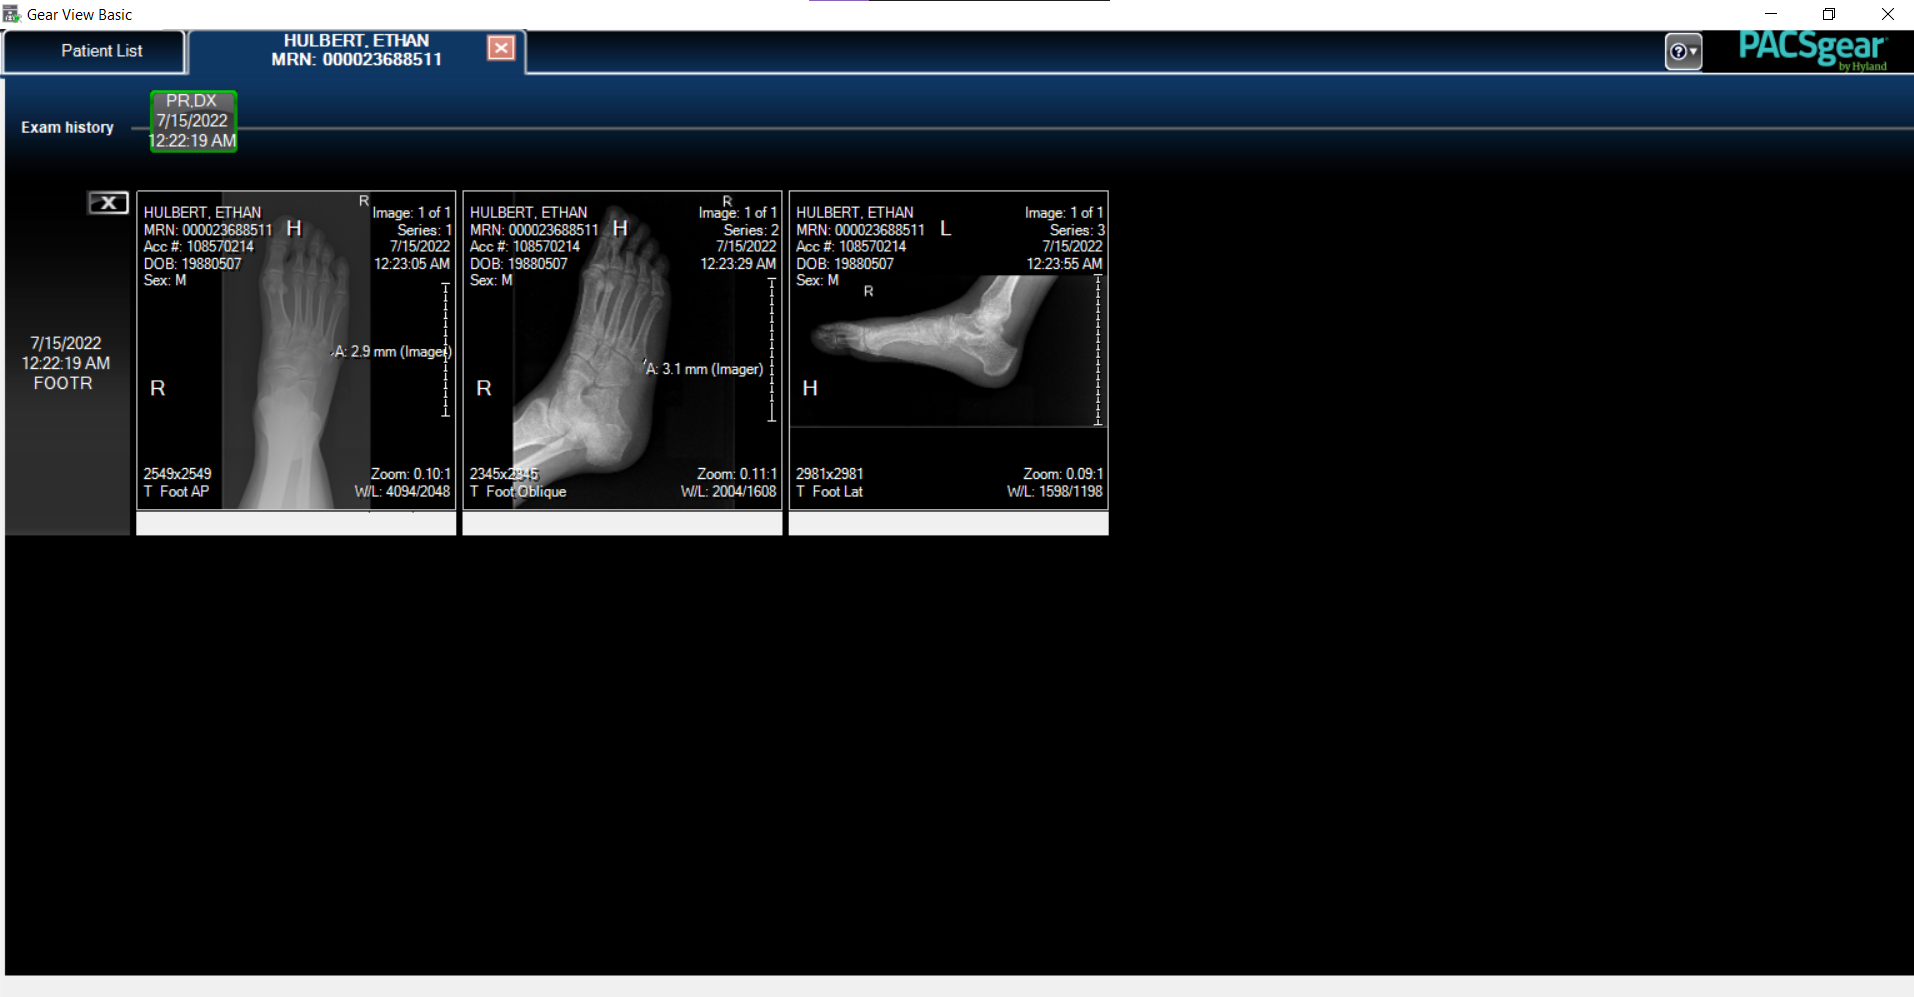

Their records department finally sent me the full disc of viewing software, too, and this is where things really got good. The software is called Gear View, and is part of the PACSgear medical imaging suite from Hyland.

Gear View Software

Here’s getting in to the program. You can imagine a doctor would have tons of patients with tons of x-rays all down this screen.

Then we can select which x-ray angle we want to drill down into.

This is the full view of a specific x-ray in a specific view. It has a little more information around it. Also, note that point A on the image is where my bone breakage occurred.

Then we can do all kinds of things to help us view the image. Here’s the menu that specifically shows me all those different view modes from above, and how I know what they’re called.

My favorite other tool lets us draw a line between two points across the x-ray, and it gives us a precise measurement! I can imagine that this would be extremely helpful for doctors and nurses. I wonder how the software matches the reference scale to the range of depth of the image that’s in focus?

You can again see where my bone was pulled apart and separated by about 3mm, too. That’s the distance of the gap. Very cool (but ouch).